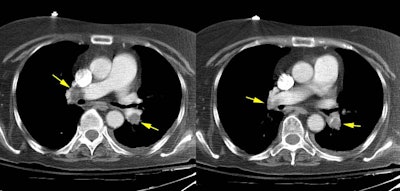

Radiology EducationResidents/FellowsMassive Pulmonary EmbolismScott WilliamsAug 28, 2001Massive Pulmonary Embolism: The case below demonstrates an example of bilateral large central pulmonary emboli (yellow arrows) Latest in Residents/FellowsRace, ethnicity influence educational debt among radiology-bound MDsAugust 15, 2025Rad residents show interest in global health imaging, but face barriersAugust 13, 2025Rad residents need more orthopedic trauma interpretation trainingJanuary 9, 2025Method quantifies improvement in resident report qualitySeptember 24, 2024Related StoriesResidents/FellowsTraumatic aortic laceration at hiatus imagesResidents/FellowsTraumatic Aortic LacerationResidents/FellowsTraumatic Aortic LacerationResidents/FellowsTraumatic Aortic Laceration